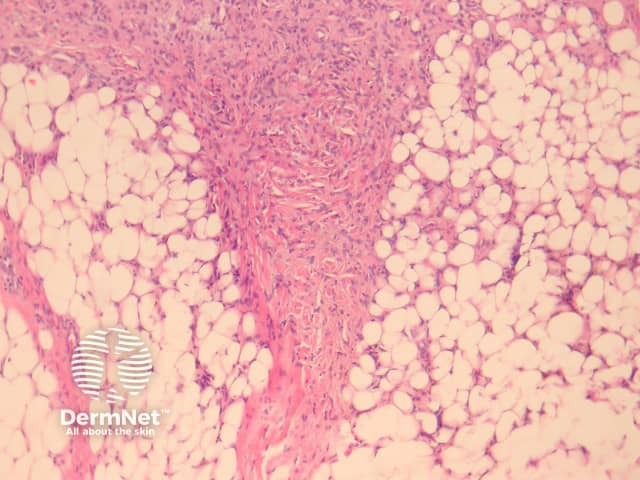

Deep fibrous histiocytoma resembles dermatofibroma histologically but affects the deep subcutis or soft tissues (figure 16). The limbs are the most frequent site followed by head and neck and then the trunk. Up to one in five deep fibrous histiocytomas recur following excision and there are 2 reported cases of metastasis and death.

Distinctive histological features of deep fibrous histiocytoma include a diffuse storiform pattern and haemangiopericytoma-like changes with staghorn-like thin-walled branching vessels in 40% of lesions. Unlike cutaneous dermatofibroma, these lesions are often CD34 positive.

Figure 16